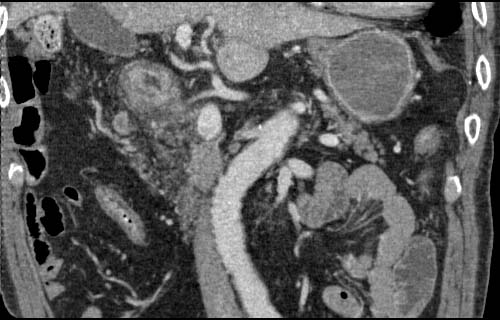

Gastric cancer / Borr.III

1mmx4, Pitch 4.5, 23 seconds, 150mAs

Data acquired & processed by H. Anno M.D.